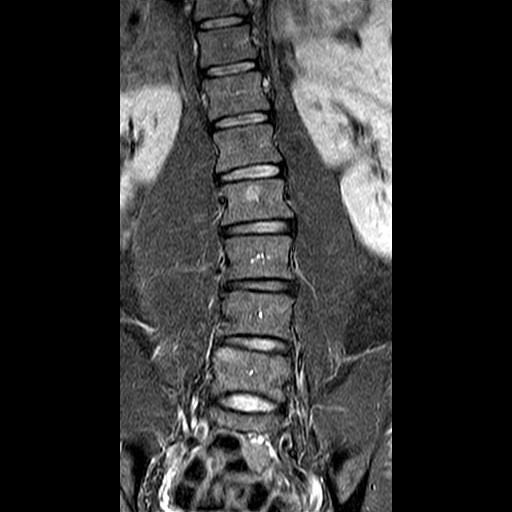

Das bringt mich zu meinem eigentlichen Punkt: Ich habe aktuelle Röntgenaufnahmen anfertigen lassen. Der zuständige Orthopäde meinte, mein Krümmungswinkel LWS läge bei 22 Grad. Vor knapp zehn Jahren hieß es, es seien 12 Grad LWS. Etwas mehr als 1 Grad Verschlechterung pro Jahr bei diesem für Skoliose-Verhältnisse geringen Krümmungswinkel - das macht mich hellhörig.

Die Röntgenbilder habe ich angehängt. Habt ihr Erfahrungen mit Messfehlern und -ungenauigkeiten? Sind diese zehn Grad Verschlechterung auch anhand der Bilder realistisch? Vielen Dank für euere Meinungen.

10 ist die alte Aufnahme, 20 die aktuelle. Das CT stammt von 2019 und wurde im Liegen angefertigt. Die RB im Stehen.

- ct.jpg (29.66 KiB) 9047 mal betrachtet